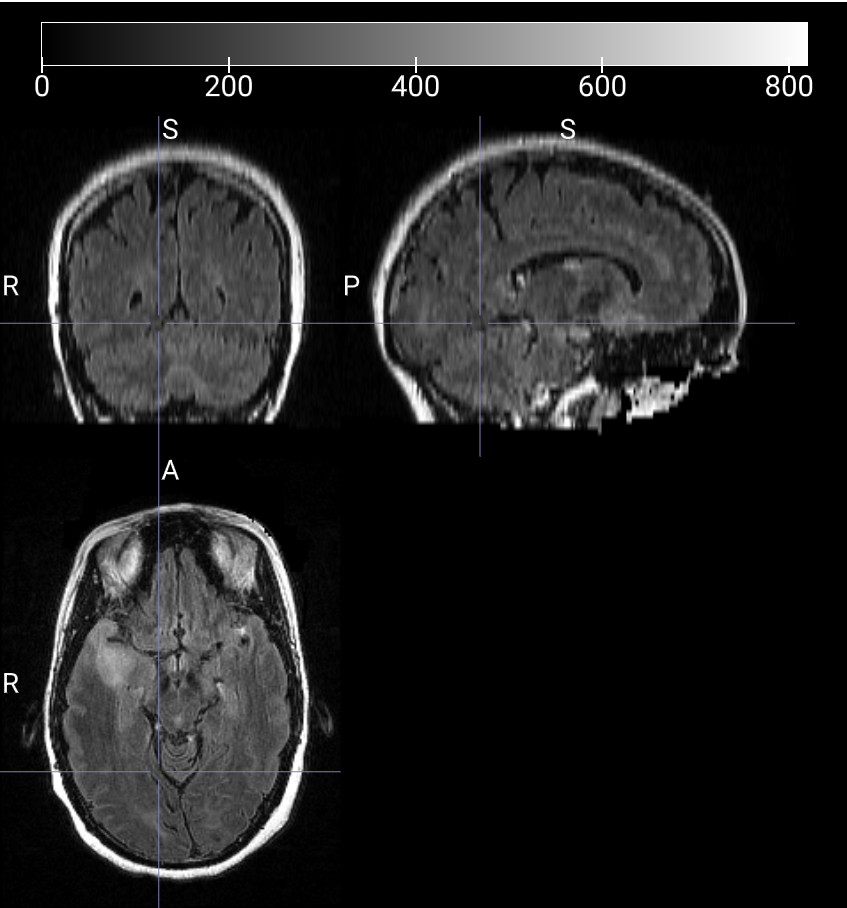

数据样本可视化

T1W 3D 对比度增强图像

T2-FLAIR 2D 图像